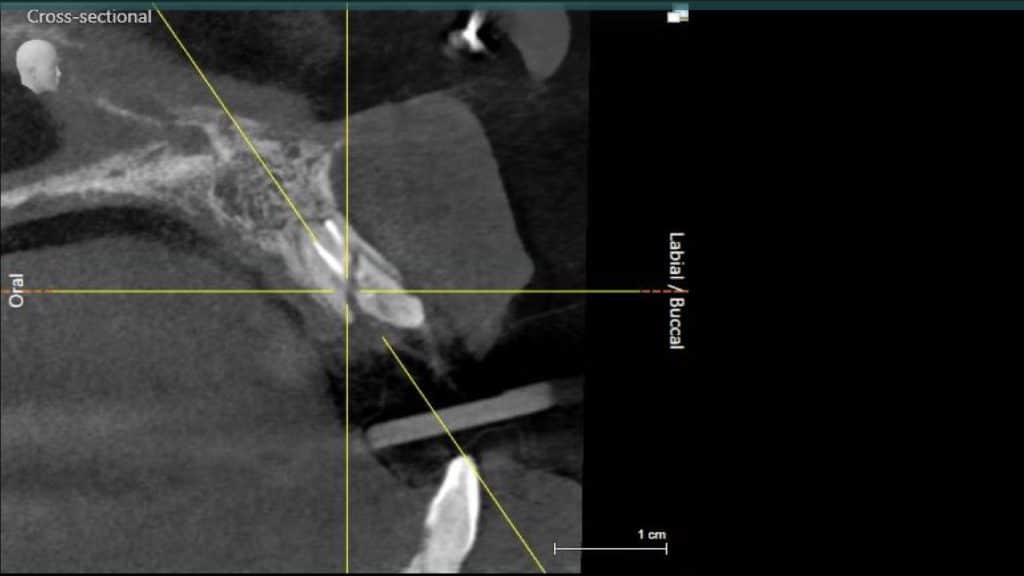

A 27-year female patient with dislodged Resin bonded FPD. She had that FPD for past few years, it had metal wings on palatal surfaces of UR1 and UL2 and a post like metal extension into the root canal of UL1. There was gingival abscess due to fractured root segment most probably due to extended metallic post like structure. Immediate implant placement (IIP) and Immediate restoration (IR) was planned for this patient.